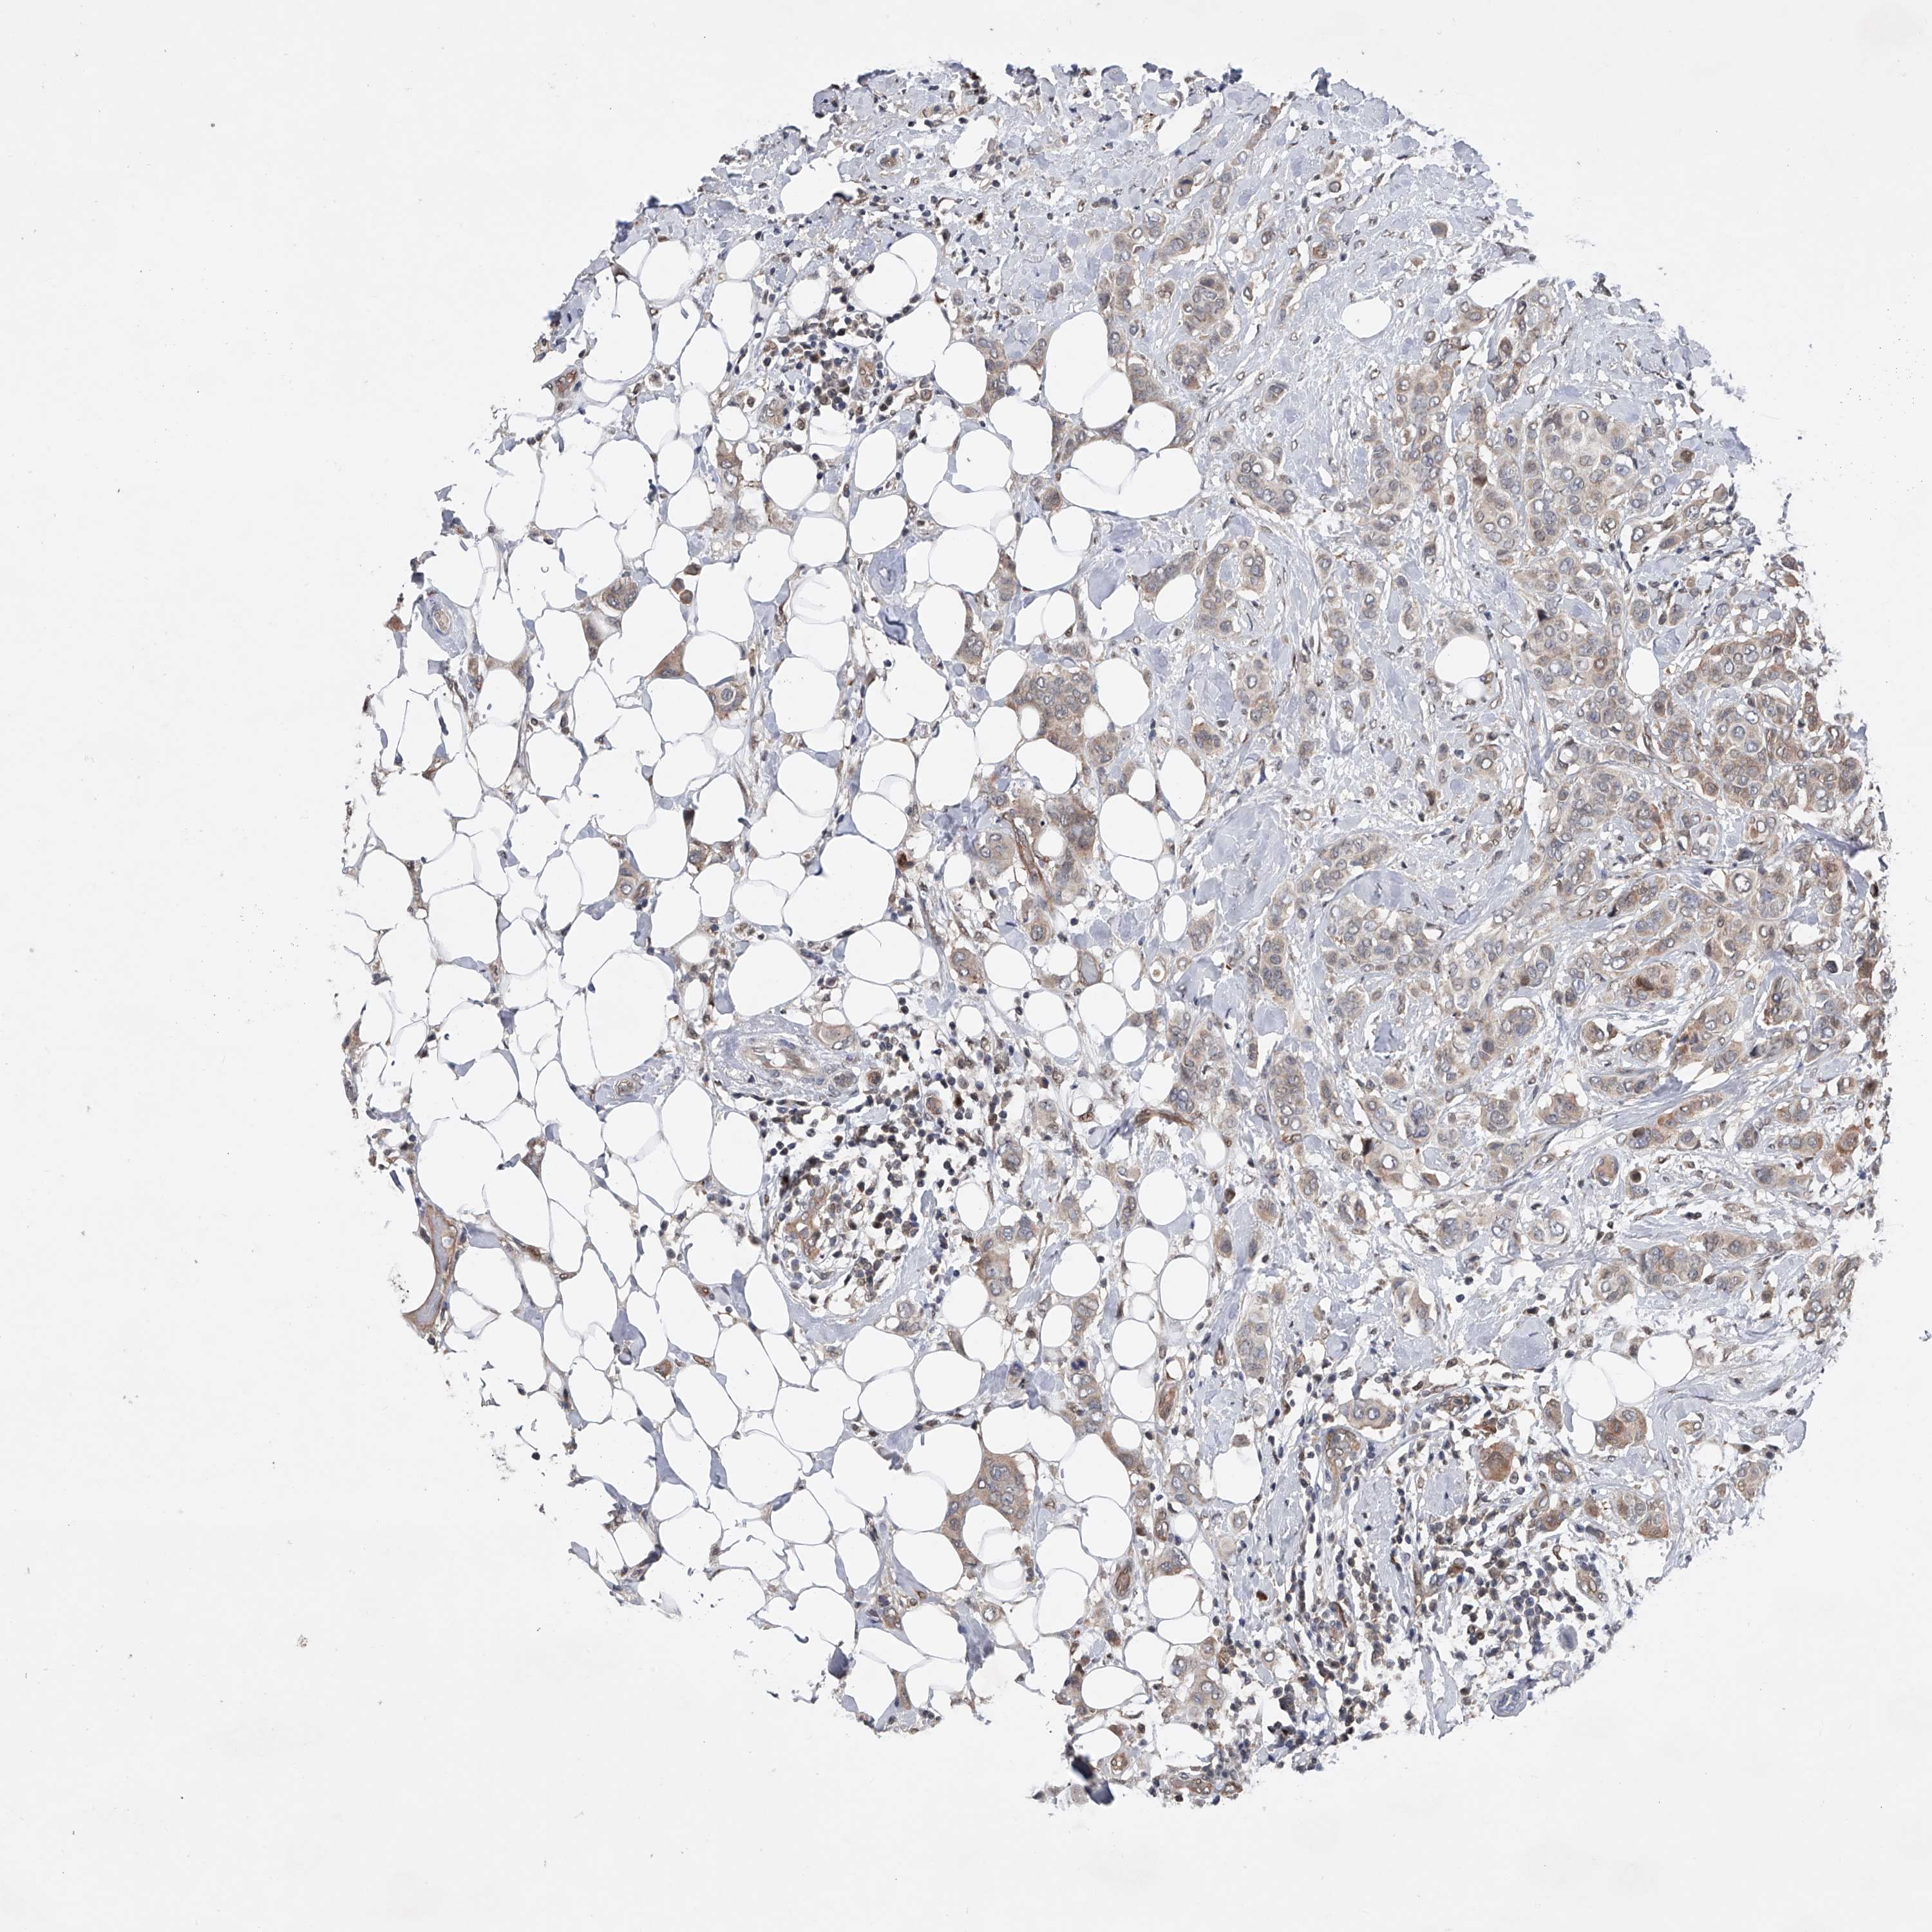

CANCER BREAST CANCER Show tissue menu

BRCA TCGA BRCA VALIDATION PROTEIN EXPRESSION